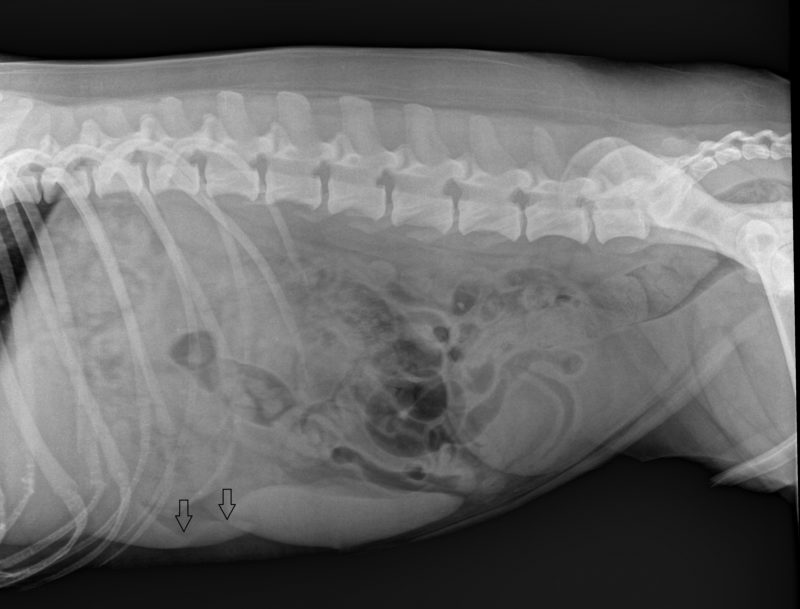

Wir vermuteten eine der letzten beiden Möglichkeiten bei unserem Patienten. Problem ist, dass der Ausführungsgang der Galle, der Ductus choledochus, beim Hund nur 2-3 Millimeter im Durchmesser misst und entsprechend schon winzige Veränderungen zu einer Einengung dieses Kanals führen. Chickos Röntgenbild zeigte lediglich eine geringgradige Vergrößerung der Leber, gab aber keinen Hinweis auf die Ursache seines Leidens. Ein Teil seiner Blutproben wurde ins Labor geschickt, um Leberschäden verursachende Infektionskrankheiten auszuschließen. Die Tests fielen jedoch alle negativ aus.